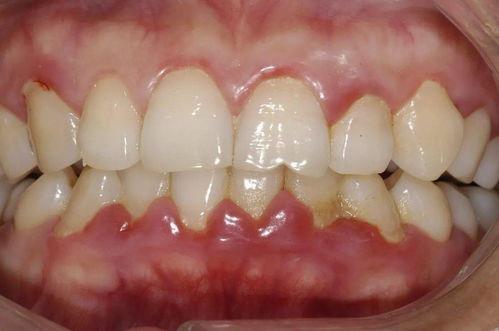

在這個(gè)階段,主要表現(xiàn)為牙齦的炎癥,牙齦紅腫、出血,尤其是在刷牙或咬硬物時(shí)容易出血。此時(shí),炎癥主要局限于牙齦組織,牙槽骨和牙周膜尚未受到明顯影響。據(jù)統(tǒng)計(jì),約70%的成年人都曾經(jīng)歷過牙齦炎。

隨著炎癥的發(fā)展,牙周組織開始受到損害。牙齦與牙齒分離,形成牙周袋,牙周袋內(nèi)堆積菌斑和牙結(jié)石。同時(shí),牙槽骨開始出現(xiàn)輕度的吸收。此時(shí),患者可能會(huì)感覺到口臭加重,牙齒有輕微的松動(dòng)。

牙周袋進(jìn)一步加深,牙槽骨吸收更加明顯,牙齒松動(dòng)度增加?;颊咴诰捉朗澄飼r(shí)可能會(huì)感到無力,甚至出現(xiàn)疼痛。此時(shí),牙齦可能會(huì)出現(xiàn)退縮,牙根暴露。